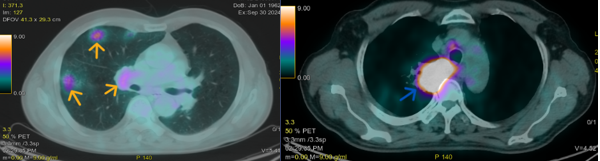

- PET/CT (30/09/2024): Hình ảnh khối mờ ở trung tâm thùy trên phổi phải xâm lấn trung thất, kích thước 70x54mm, tăng chuyển hóa FDG (SUVmax 38.6); Vài đám mờ kính thùy trên phổi phải kích thước 25x22mm, tăng chuyển hóa FDG (SUVmax 8.78); Vài hạch trước khí quản, trước carina, dưới quai động mạch chủ, hạch lớn nhất có đường kính 10mm, tăng chuyển hóa FDG (SUVmax 6.47); Vài hạch rốn phổi phải, hạch lớn nhất có đường kính 11mm, tăng chuyển hóa FDG (SUVmax 5.2); Vài hạch hố nách hai bên đường kính <10mm không tăng chuyển hóa FDG.

Hình 5. Hình ảnh khối mờ trung tâm thùy trên phổi phải xâm lấn trung thất (mũi tên xanh) kích thước 70x54mm, tăng chuyển hóa FDG (SUVmax 38.6); Vài đám mờ kính thùy trên phổi phải (mũi tên vàng) kích thước 25x22mm, tăng chuyển hóa FDG (SUVmax 8.78).

Hình 6. Vài hạch trung thất(mũi tên vàng) hạch lớn nhất có đường kính 11mm, tăng chuyển hóa FDG (SUVmax 5.2).